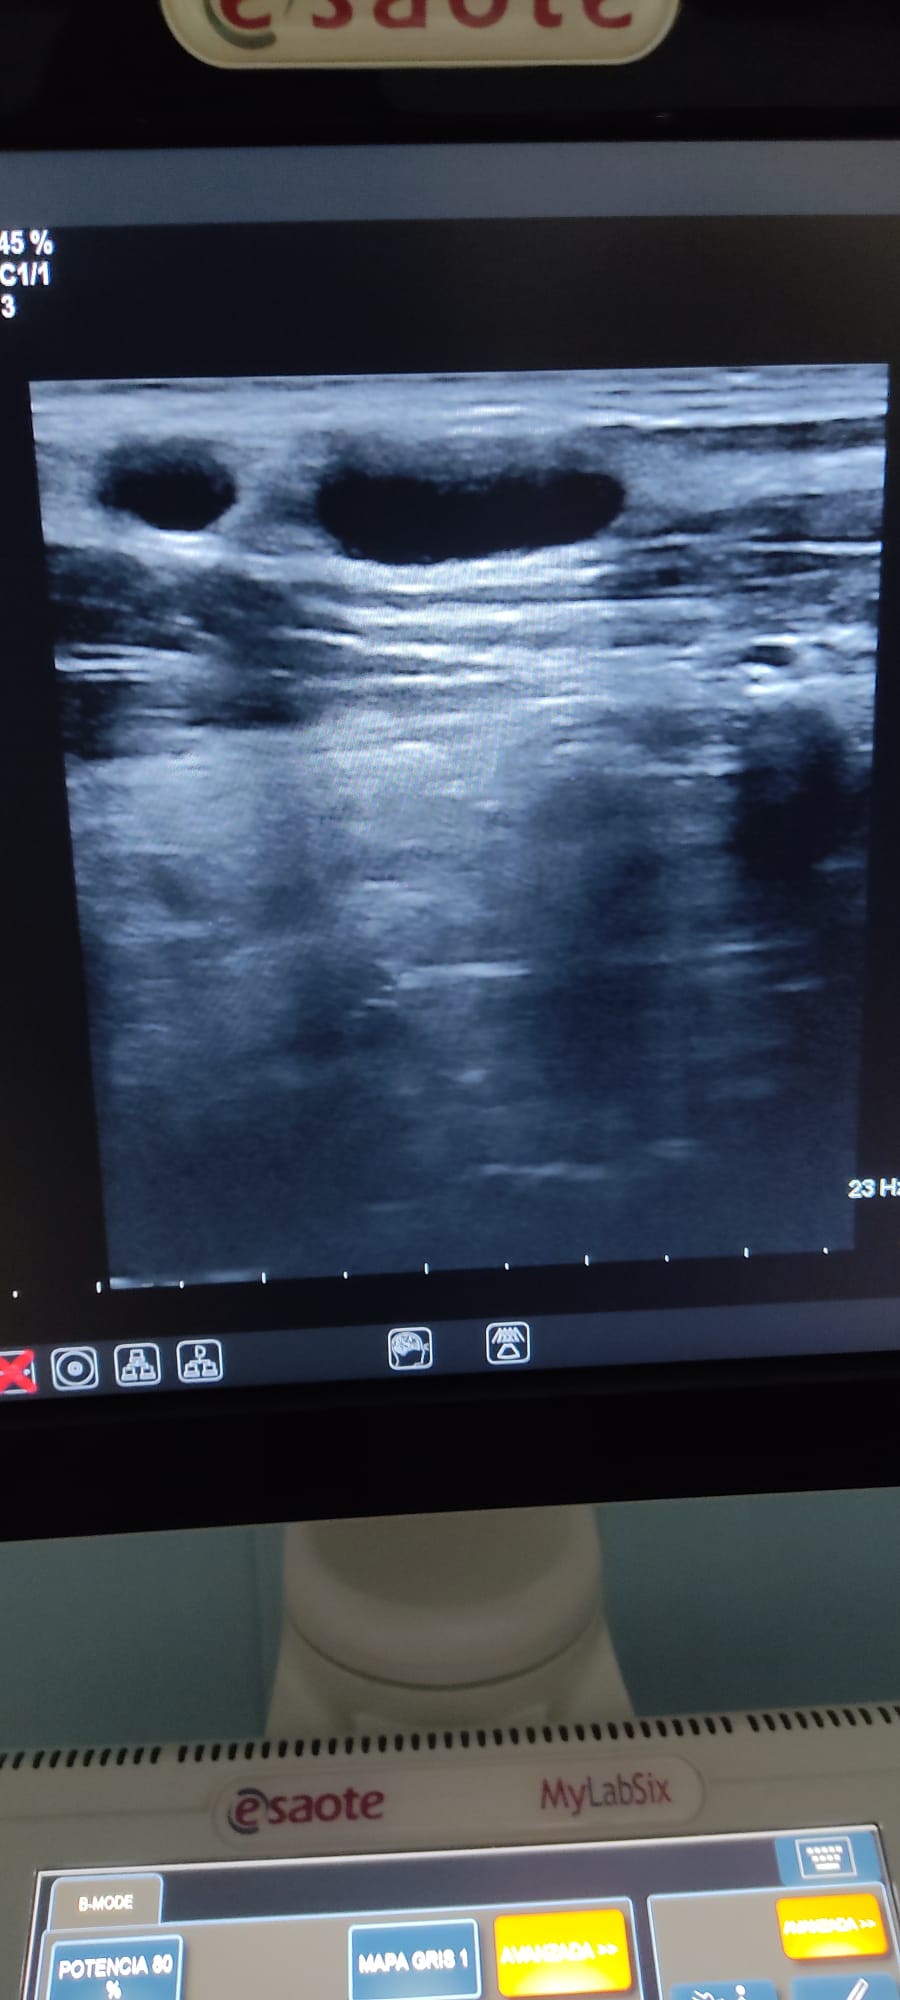

Se le realiza una Ecografía clínica a pie de cama (POCUS), donde se observan múltiples adenopatías anecoicas en ambas cadenas submandibulares y laterocervicales, algunas de 3 cm aproximadamente, de aspecto redondeado y con sugestiva presencia de hilio.